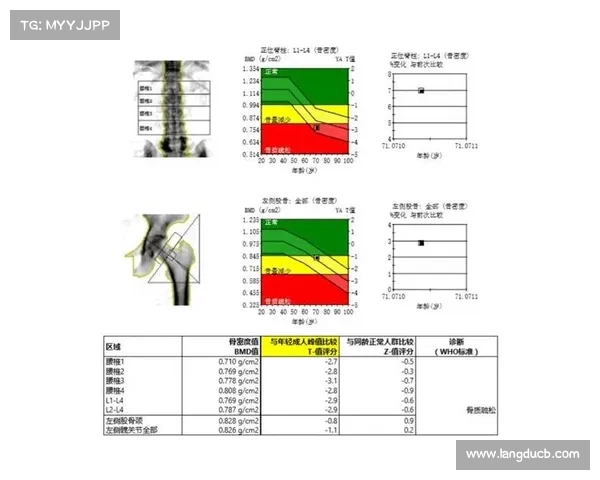

常用的骨骼密度监测方法包括双能X线吸收测定法(DXA)和定量计算机断层扫描(QCT)。这些技术能够精确测量骨骼中的矿物质含量,帮助医生和训练师评估球员的骨骼健康状况。对于大体重球员,监测频率通常建议为每1-2年一次,高风险群体甚至可能需要更频繁的检查。